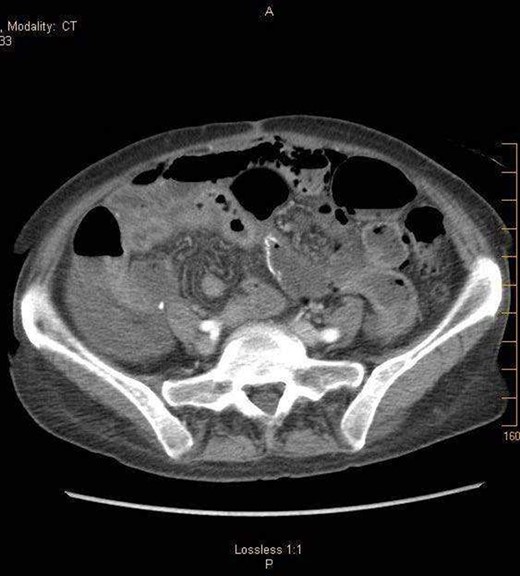

A 57-year-old non-toxic appearing female with a medical history of diverticulosis and malnutrition, and a surgical history significant for small bowel obstruction due to jejunal lymphangioma status post exploratory laparotomy and resection of bowel (2.2018). This patient presents with epigastric pain ×2 days with radiation to left upper quadrant and nausea with emesis, concerning for obstruction. In the Emergency Department, the patient was non-toxic appearing, hemodynamically stable, with no leukocytosis (7.4), or elevated lactic acid (1.2). Imaging, XR (Fig. 1) and CTAP (Fig. 2), demonstrating SBO with free air concern for perforated viscus. The concern for free air on imaging, in the setting of abdominal pain with symptoms of obstruction, mandated an operative intervention. On 7.5.18 the patient underwent exploratory laparotomy and was found to have emphysema of proximal jejunum, and underwent 125 cm resection of jejunum (Figs 3 and 4). Pathology of the specimen demonstrated multiple air filled cystic serosal nodules consistent with PCI (Figs 3 and 4, Supplementary Fig. S7).

7.4.18:CTAP w/IV and PO contrast: suggestive for small bowel obstruction, distal small bowel collapsed, mild or moderate free air suggestive of perforated viscus, free fluid in dependent portion of pelvis.